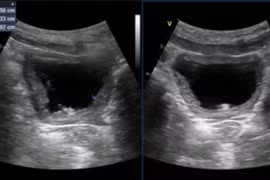

Sỏi thận và sỏi tiết niệu

(khoahocdoisong.vn) - Sỏi thận, sỏi tiết niệu là bệnh rất phổ biến trên thế giới, đặc biệt là ở Việt Nam. Theo thống kê, tỷ lệ điều trị bệnh sỏi tiết niệu (sỏi thận, sỏi niệu quản, sỏi bàng quang, sỏi niệu đạo) tại khoa thận – tiết niệu chiếm trên 40%.